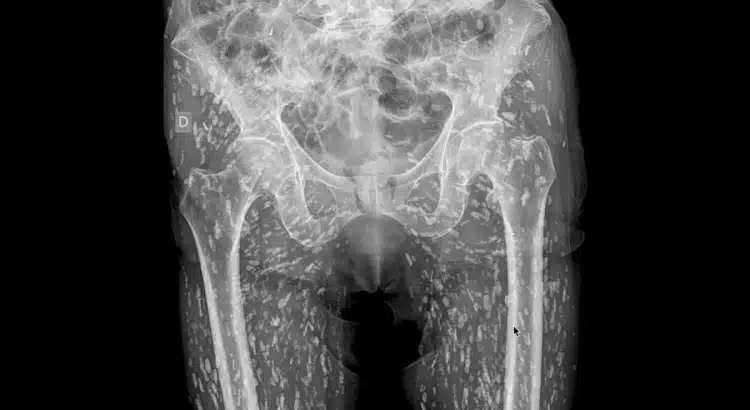

Des semaines plus tard, après une chute sans gravité, il décide de consulter pour des douleurs persistantes à la hanche. Lors de la radiographie, les médecins découvrent quelque chose d’effrayant : son corps est infesté de kystes parasitaires causés par un ver solitaire.

Lorsqu’ils ont analysé la radiographie, les médecins ont trouvé des dizaines de petites masses dans les tissus mous des jambes et des hanches. Certaines étaient inoffensives, mais d’autres risquaient de provoquer des infections graves. Si les larves atteignent le système nerveux central, elles peuvent entraîner une neurocysticercose, une forme de la maladie qui cause des symptômes neurologiques comme des crises d’épilepsie.